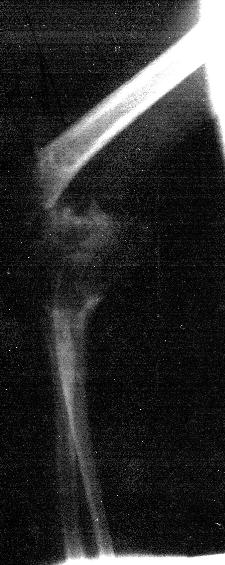

Fractura supracondílea

Imagen de la radiografía

Fractura supracondílea brazo derecho. Pablo, 15 meses